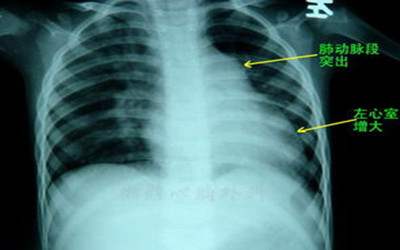

七大並發症!高血壓患者需警惕     一、冠心病     高血壓是冠心病的主要危險因素之一,高血壓病病人患冠心病的危險是正常者的2倍,長期高血壓不治療,有50%死於冠心病。 七大並發症!高血壓患者需警惕     二、糖尿病     在糖尿病人群中,高血壓的發病率是正常人群的2倍。糖尿病與高血壓並存相當常見,它是病人發生動脈硬化和腎功能衰竭的重要原因。     三、心力衰竭     心力衰竭是高血壓的常見並發症,流行病學研究表明40%—50%的心衰起因於高血壓。血壓越高,又沒有治療,發展為心衰的可能性越大。有人對5314例高血壓病人隨訪14.1年,有392例發生心衰,高血壓已被認為是導致左心室肥厚和心肌梗塞的主要危險,而左心室肥厚和心梗可引起心髒功能不全,因此,高血壓在心衰歷程中起著重要作用。 七大並發症!高血壓患者需警惕     四、腎病     在人類,腎髒參與高血壓的形成與維持,反過來,腎髒又因血壓升高而損害,長期高血壓沒有治療,可引起終末期腎功能衰竭,或加速腎實質的破壞導致原發或繼發的腎髒疾病。 七大並發症!高血壓患者需警惕     五、周圍動脈疾病     高血壓使間歇性跛行的危險增加3倍,可能是因為血壓升高使某些特定的部位如下肢動脈、頸動脈、冠狀動脈硬化加速,導致下肢動脈發生缺血、營養障礙,甚至壞死。     六、中風     高血壓腦卒中的發生率是正常血壓的7.76倍,還有研究表明,降壓治療可使中風發生率降低40%,冠心病危險降低15%。     七、左室肥厚     在所有高血壓病人中,有20%—30%可查到左室肥厚,輕度高血壓患者發生左心室肥厚比正常血壓增多2—3倍,而重度高血壓可達10倍。左心室肥厚是心梗的一個潛在危險因素,並影響左室收縮功能,因此高血壓左室肥厚是一個與心血管發病率和死亡率密切相關的重要危險因素。 七大並發症!高血壓患者需警惕     溫馨提醒:高血壓有許多合並症或與許多疾病並存,若不及時堅持有效的治療高血壓,可大大增加心腦血管病的發生率和死亡率。     本文來自網絡,版權為原作者所有,如有侵犯權益,請聯絡我們刪除。